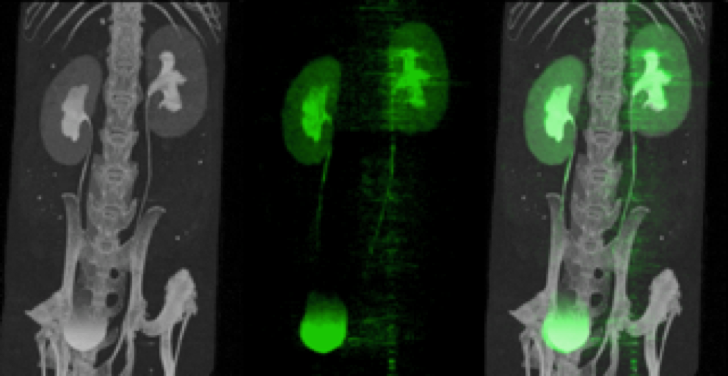

Construction de PIXSCAN-FLI, un troisième prototype de scanner à comptage de rayons X financé par France Life Imaging (FLI), qui est évalué dans le cadre de projets conjoints consacrés à l'imagerie longitudinale de tumeurs hépatiques spontanées chez la souris avec l'Institut de biologie du développement de Marseille IBDM.

- F. Cassol et al. Tracking dynamics of spontaneous tumours in mice using Photon Counting Computed Tomography. iScience 21 (2019) 68-83

- F. Cannet, C. Sequera et al. Tracing specificity of immune landscape remodeling associated with distinct anticancer treatments. iScience 28 (2025) 112071